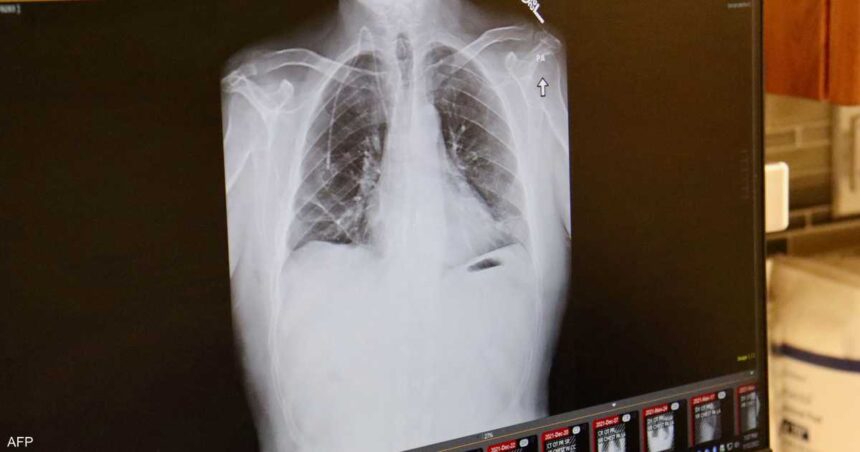

ويضيف أن سرطان الرئة، وخصوصا السرطان الغدي ( نوع من السرطان يبدأ في الغدد التي تفرز مواد مثل المخاط أو السوائل في أنسجة الجسم وقد يصيب الرئة)، لا تظهر أعراضه في المراحل الأولى، مثل السعال وألم الصدر وضيق التنفس، إلا عندما يكون الورم قد انتشر، ولهذا تشخص أغلب حالات هذا المرض في مرحلة متقدمة.

وأشار تقرير لـ”بي بي سي”، إلى أن نسبة الإصابة بسرطان الرئة تزداد كل سنة، وهو أكثر شيوعا بين النساء، خاصة من أصول آسيوية، معتبرا أن للهرمونات الأنثوية تأثيرا على ظهور هذا النوع من السرطان”.